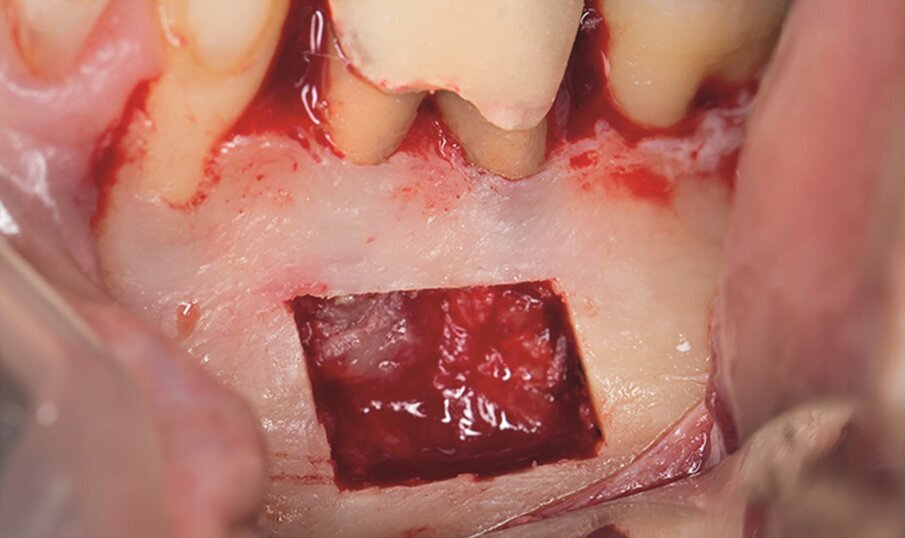

Under local anaesthesia, a full-thickness mucoperiosteal‑ap was reflected, providing visualisation of the buccal bone (Fig. 2g), and the printed template was used to mark the cortical window (Fig. 2h), which was cut with a Piezotome CUBE LED handpiece, and the separated instrument was exposed (Fig. 2i) and removed (Fig. 2j). After apicectomy, retro-preparation was done using ultra sonic tips (ACTEON) and sealed with TotalFill BC RRM Fast Set Putty (FKG) (Fig. 2k). The ‑ap was sutured using 5/0 prolene suture material (Fig. 2l). The sutures were removed 72 hours postoperatively. After two years the patient came to our office for a follow-up radiograph, the tooth was asymptomatic and in function (Fig. 2m).

Fig. 2g: Full-thickness mucoperiosteal flap reflected.

Fig. 2h: The template was adjusted and the limits of the cortical window were marked in the bone.

Fig. 2i: Separated instrument out of the root near the apical area of tooth #15.